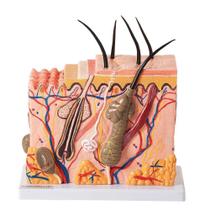

Gente, os modelos anatômicos e simuladores são cópias exatas de diferentes órgãos do corpo de humanos e dos animais, que servem pra professores e outros profissionais mostrarem como funcionam os sistemas do corpo. Eles imitam a estrutura interna e externa do organismo e também são usados pra treinamentos práticos! Quer saber mais sobre eles? Vem comigo que eu te conto:

Gente, os modelos anatômicos e simuladores são cópias exatas de diferentes órgãos do corpo de humanos e dos animais, que servem pra professores e outros profissionais mostrarem como funcionam os sistemas do corpo. Eles imitam a estrutura interna e externa do organismo e também são usados pra treinamentos práticos! Quer saber mais sobre eles? Vem comigo que eu te conto:

- Olha, os modelos anatômicos e simuladores são usados em áreas como Medicina, Enfermagem, Fisioterapia e Veterinária pra imitar órgãos como o coração, rins, útero, olhos, cérebro, as articulações e até o esqueleto inteiro.

- Esses modelos são feitos de resina ou de propiletileno, que é um plástico mais duro, e são desmontáveis, pra apontar todos os detalhes dos órgãos, como camadas, veias e nervos.

- Agora, o simulador pode imitar adultos, idosos e crianças de corpo inteiro ou apenas uma parte dele, como a perna, a cabeça, o pé ou o tronco.

- E tem modelos que vêm com recursos digitais, como programas que reproduzem situações de risco de vida e que indicam quando o procedimento está sendo feito da forma certa. Legal!

Aqui no Magazine Luiza tem vários modelos anatômicos e simuladores. Vem ver!